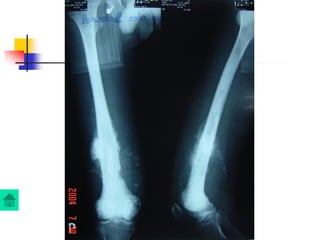

Giai đoạn mãn tính

Viêm xương chấn thương

Chẩn đoán

Lâm sàng:

Dò mủ kéo dài, đau nhức ít, không sốt hoặc sốt âm

ỉ, sưng nề khu trú

Xquang: Có thể thấy xương chết, xương tù, phản

ứng tạo xương ngoài màng xương